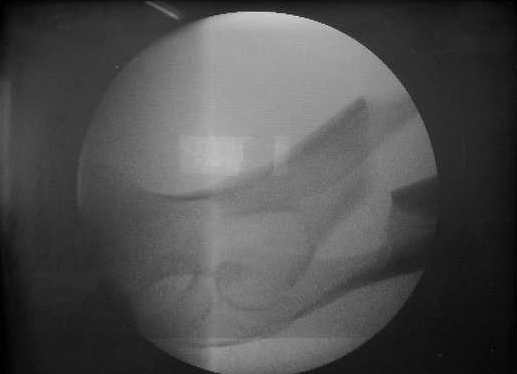

Спицы оставлять не надо. Надо их убрать, но перед этим ввести винт-poller. Такая необходимость возникает в редких случаях, когда можно ожидать смещения длинного отломка. Спицы из короткого отломка после введения запирающих винтов можно удалять без риска смещения.

В приложении пример, дистальный отломок пружинил кзади. Два винта потому, что первый оказался чуть кпереди и не упирался в гвоздь.